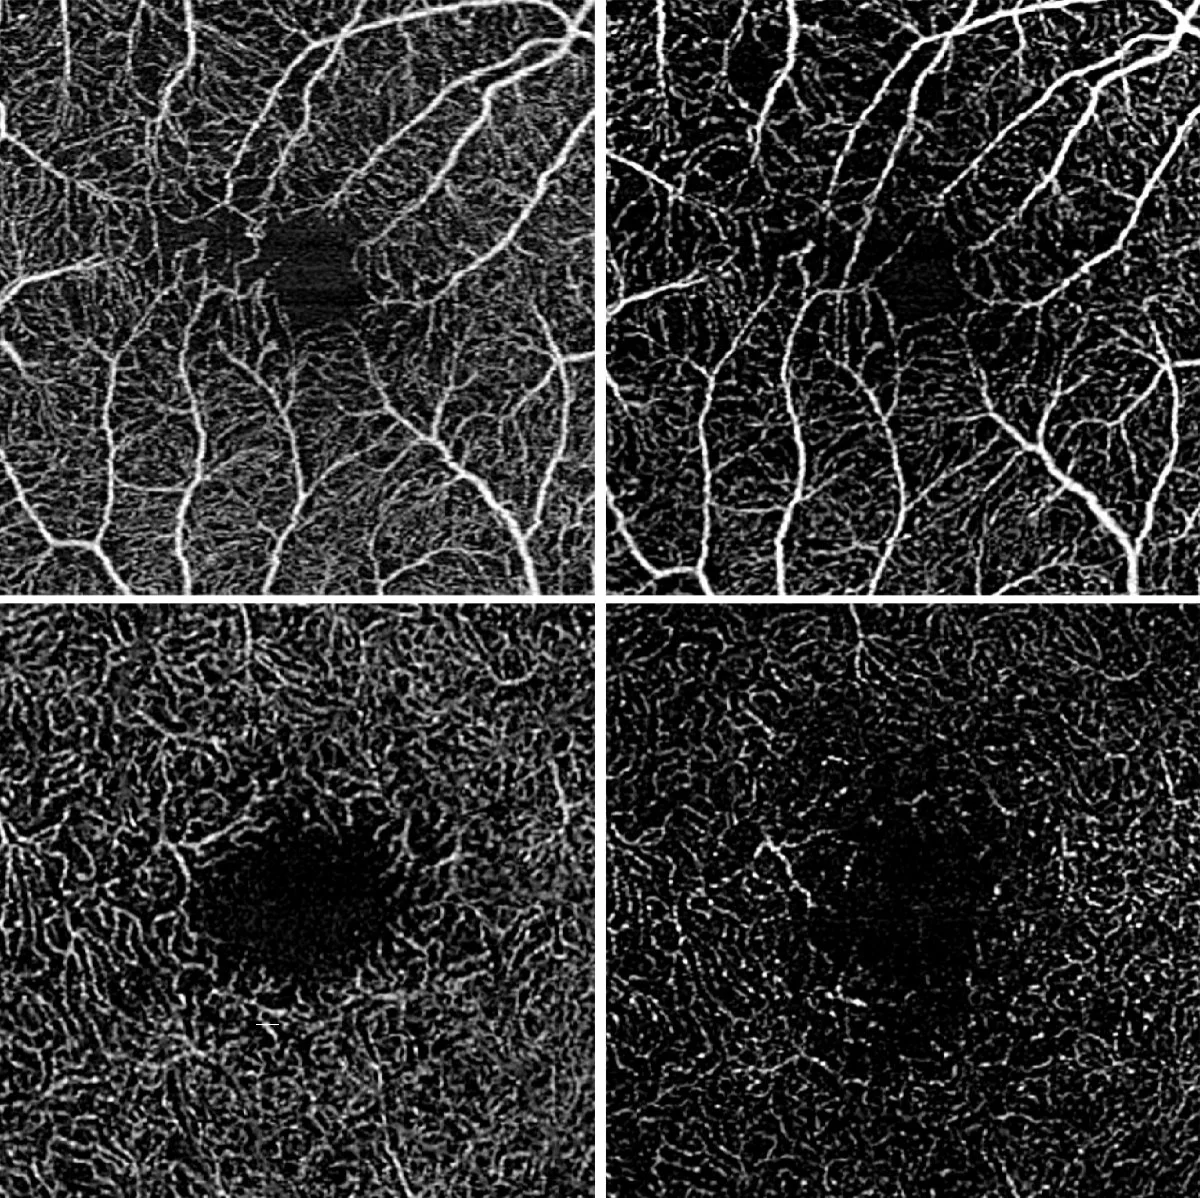

Optical coherence tomography angiography showing ocular vascular perfusion in intermediate uveitis:

The upper images show the superficial and the lower images the deep retinal blood flow. The initial state is shown on the left and the state after disease worsening is shown on the right. The blood flow density has decreased in both the superficial and deep retinal layers.